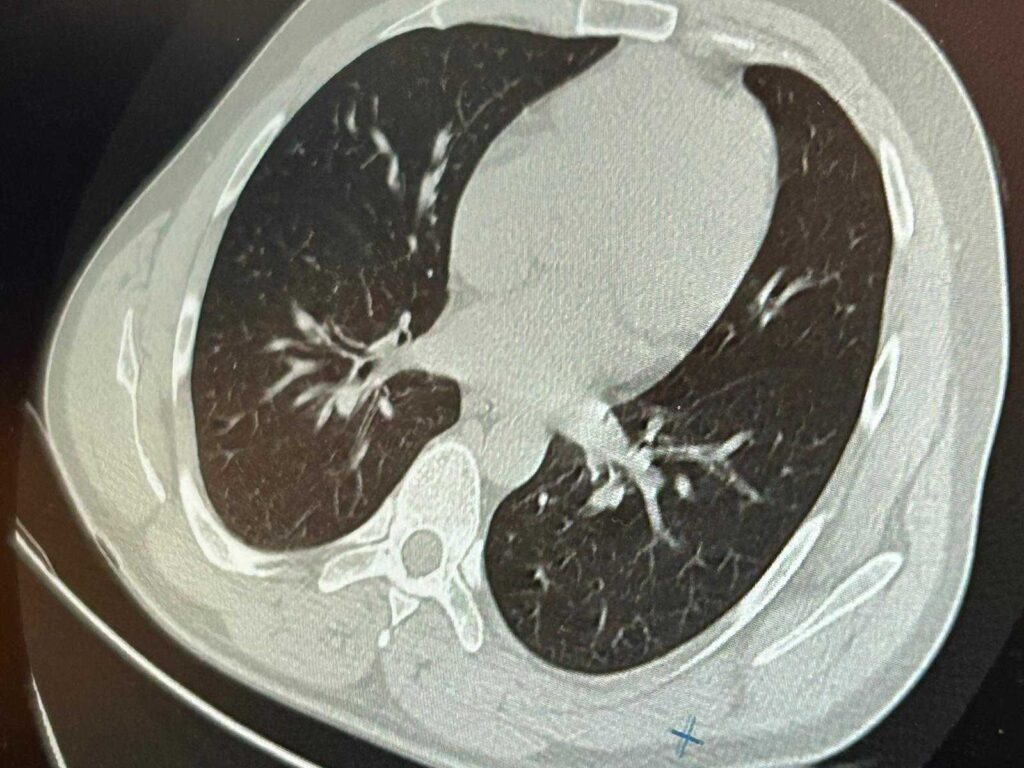

Göğüs Cerrahisi uzmanları Op. Dr. Sadullah Aksoy ve Op. Dr. Beniz İrem Ersoy Şığva’nın müdahalesiyle hastaya acil bronkoskopi uygulandı. Yapılan görüntülemede, implant vidasının sol akciğerin üst lobundaki bronşlardan birine saplandığı tespit edildi. Vidanın özel yapısı ve bulunduğu bölge nedeniyle çıkarılması oldukça güçleşti.

“Hasta bize ulaştığında genel durumu iyiydi, ancak solunum yollarından birinde tıkanıklık söz konusuydu. Bronkoskopi sırasında, vida parçasının akciğerin dar bir bronşuna saplandığını gördük. Taş kırma cihazlarına benzer bir teknikle müdahale ettik. İlk denemede çıkaramadık ama yerinden oynatabildik.”